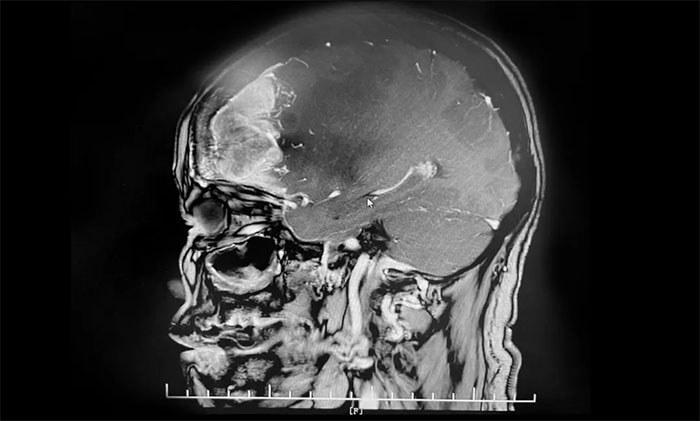

入院后,于耀宇主任為章女士完善檢查。頭顱MRI增強(qiáng)示:右側(cè)額葉不規(guī)則團(tuán)塊狀異常信號(hào)影,邊界不清,最大直徑約5.6cm,大小與鴨蛋相仿。病灶周邊有大片水腫信號(hào)影;鄰近大腦腳、胼胝體及雙側(cè)側(cè)腦室受壓、變形;中線結(jié)構(gòu)左偏。

▲ 腫瘤大小與鴨蛋相仿